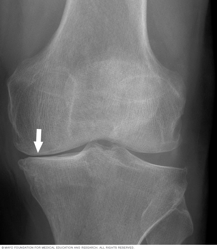

X-ray of knee arthritis

Knee arthritis can affect one side of the joint more than the other. This X-ray image shows how the cushioning cartilage has worn away, allowing bone to touch bone.